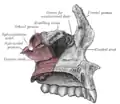

Le processus frontal gauche représenté en rouge.

Le crâne de face. Coupe sagittale du crâne.

Coupe sagittale du crâne. Toit, plancher et paroi latérale de la cavité nasale gauche.

Toit, plancher et paroi latérale de la cavité nasale gauche.- Processus frontal du maxillaire